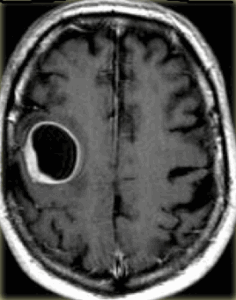

При МРТ головного мозга на Т2-зависимых МРТ выявляется узловое гиперинтенсивное образование, как правило, больших размеров, отек слабо выражен, границы нечеткие, структура неоднородная. Последнее связано с кальцификацией (50-90% случаев), кровоизлияниями, центральным некрозом и кистами. Контрастное усиление при МРТ наблюдается примерно в половине случаев, обычно при более злокачественных вариантах, особенно если контрастирование идёт по кольцевидному типу. Отличить олигодендроглиому от астроцитомы очень трудно. В пользу олигодендроглиомы говорят поверхностное расположение, кальцификация (доказывается с помощью КТ) и слабая выраженность отека при МРТ. МРТ в СПБ при опухолях мозга профессор Холин А.В. проводит преимущественно на разных типах МРТ. Среди центров МРТ СПб мы специализируемся нв выявлении различных опухолей.

МРТ головного мозга. Олигодендроастроцитома. Аксиальная Т2-зависимая МРТ.